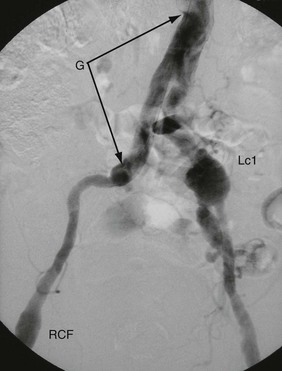

A false aneurysm is the result of a slow anastomotic leak or a leak from an arterial puncture (e.g. a femoral artery puncture for coronary artery stenting) that is confined by surrounding tissues. A slowly expanding blood-filled cavity results, which can eventually rupture or undergo thrombosis. A false aneurysm usually presents as a palpable pulsatile mass. False aneurysms following a femoral artery puncture can be observed (if < 2 cm diameter they can thrombose of their own accord), treated percutaneously with injection of thrombin, or repaired surgically. Patients are often taking dual anti-platelet therapy and have advanced coronary artery disease, the reason for the angiogram in the first place.

False aneurysms also can occur at an anastomosis (usually between a synthetic graft and artery). They used to be more common because of gradual breakdown of silk suture materials, but can still occur, sometimes as a consequence of low grade infection. They often require surgical reconstruction.

Occasionally a false aneurysm at an upper anastomosis of a graft with the abdominal aorta leaks into the overlying duodenum. This produces an aortoduodenal fistula and presents with major haematemesis. Aortoduodenal fistula may also result from graft infection.